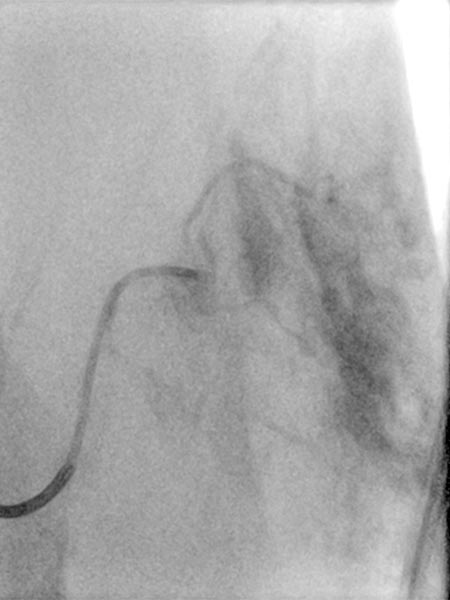

As there was still no tendency to regression of the tumor at the end of the 3rd year, embolization was performed after biopsy to induce involution. Digital subtraction angiography (DSA) shows a microcatheter superselectively introduced into a tumor vessel. The tumor is heavily perfused and lobulated, very early venous outflow, typical of an NICH.

Particle embolization with spherical particles 250 micrometers in size via the microcatheter inserted superselectively into the tumor.